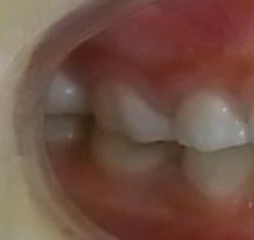

7歳の女子 受け口(下顎前突)

術前

術後

いずれも、顎のラインがスッキリしています。

これは、受け口が改善して筋肉の使い方が通常に戻ったために起こった変化です。

大人ではこの変化は起こりません。